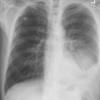

huge effusion PA